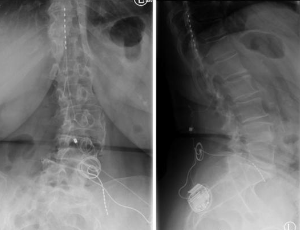

What is the Time Necessary to be Able to Place Transpedicular Screws According to the Chosen Technique?

Transpedicular screw placement techniques are technically plaintiffs have relied on navigation intraoperative which is limited by its high cost, limited use of a fluoroscope with the radiological overexposure of the personnel of health and patient offers limited help when placing screws, and vertebral anatomical modifications especially in patients with degenerative pathology result an index of placement-related complications suboptimal of the screws [1,2].

Since its introduction by Roy-Camille [3] and Louis [4] in the seventies, the use of screws pedicle has increased markedly to the present day